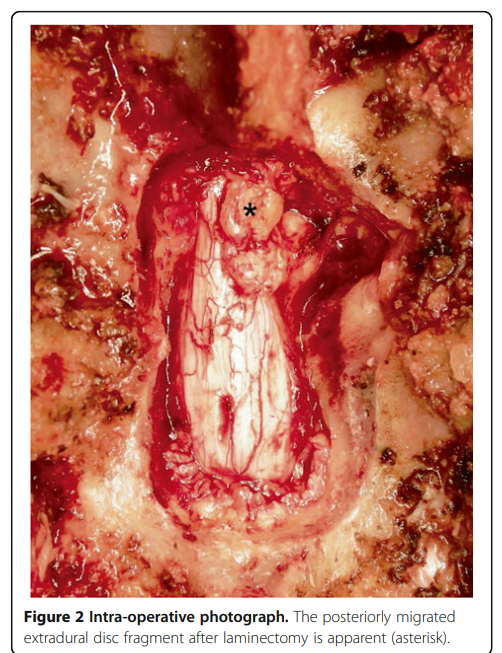

Miyakoshi N, Hongo M, Kasukawa Y, Ishikawa Y, Shimada Y. Posteriorly migrated thoracic disc herniation: a case report. J Med Case Rep. 2013 Feb 12;7:41.

适应症:侧方型软性TDH或移位到硬膜囊侧方或背侧的游离型TDH该病案报道了一例极为罕见的T9-10椎间盘脱出后移至硬膜后外侧,行T9-10右侧椎板切除术。术者行显微镜手术而非内镜手术,但现有内镜微创技术可以完成该操作。

术中探查为椎间盘髓核在硬膜背侧需要注意的是与硬膜外脓肿、硬膜外血肿、滑膜囊肿和硬膜外肿瘤的鉴别诊断,因为胸椎间盘脱出移位至背外侧是极其罕见的,往往需要行增强MR:1.神经系统症状为突发;2.硬膜外血肿:患者实验室凝血功能往往存在异常,但自发性血肿凝血功能可能正常,但早期血肿通常不会呈现增强信号,因为与血肿相关的边缘强化信号改变通常可见于其溶解状态;3.肿瘤或滑膜囊肿:一般来说,肿瘤或滑膜囊肿引起的神经系统并发症是逐渐发生的,且往往有相应病史。